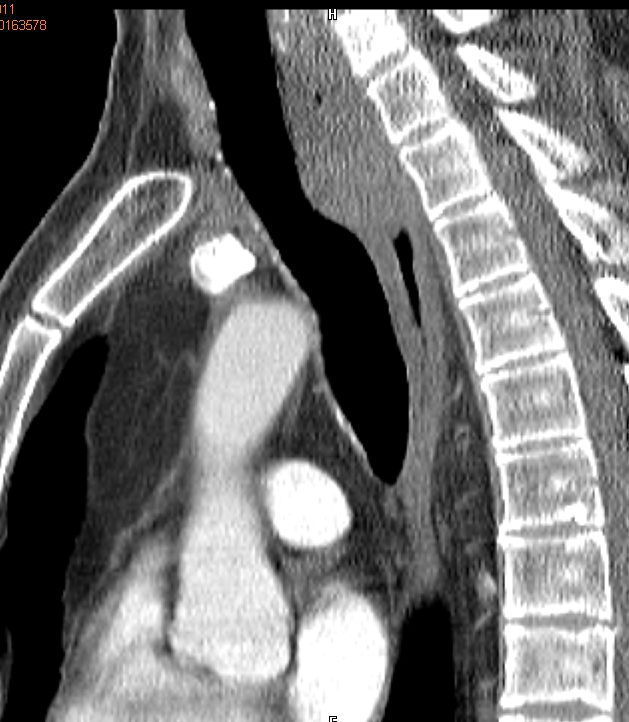

Rezidiv nach Radiochemotherapie eines kleinzelligen Tracheakarzinoms mit großer supraclavikulärer Metastase | |||